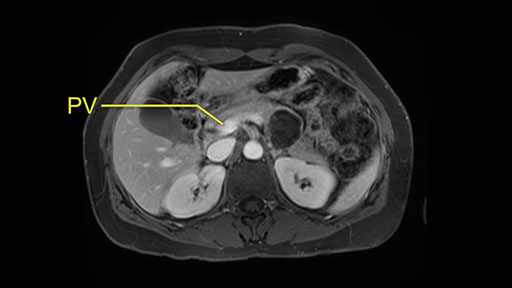

The slowing down moments or considerations that I give when I look at the scan and plan my distal pancreatectomy is how far away the tumor is to the portal vein and do I have to formally create a tunnel behind the pancreas on top of the portal vein or do I have to take the pancreas further to the left of the portal vein or the patient’s left of the portal vein. So here I can see that here is the tumor here. I can see that the tumor is a fair way away to the patient’s right and so I will likely not have to take or create the tunnel formally in this procedure. And that speaks a lot to the resection margins. So its important when you’re doing a distal pancreatectomy or any procedure potentially for oncologic reasons to get clearance of the tumor and to take the tumor kind of intact.

Key features that I look at the imaging are: first I look at the distance between the cyst and the portal vein SMV confluence. So there are guidelines for this, they call the Yonsei guidelines, to decide to do it laparoscopically or open and basically it says that if it’s a cancer, at least a centimeter away from the celiac trunk or the venous confluence. This is a cyst. So maybe you could stretch that a bit, but you don't want to get into trouble there. So for this cyst if you look at it, it's nicely away from the confluence.

So unfortunately I cannot show you a coronal view but you can see it easily on this scan, going down first you see the celiac trunk and you see here, quite a nice distance between the celiac trunk and the beginning of the mucinous cyst. And if you go up here and follow down the portal vein confluence you also see a nice distance there.

So what I would normally do in these patients, I would look at the abutment of any other organs, one, which is here, potentially the adrenal gland and two the small bowel. And two, look at the distance from the vessels which I would normally do in a coronal view. So you can easily measure the distance and third I look at the insertion of the inferior mesenteric vein. Now we can probably also see that on here. Although it's better on a CT scan and it's better on a coronal view, you want to know where the inferior mesenteric vein comes into either the splenic or the SMV, because that is typically a very important slow down moment when you mobilize the lower portion of the pancreas knowing where the inferior mesenteric vein comes in either the splenic vein or the SMV. So those are I think the three most important points for the CT scan.